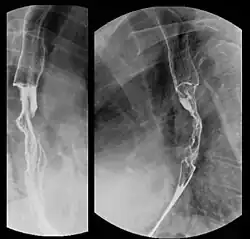

Röntgen-Breischluckuntersuchung: Die normale glatte Kontur der Speiseröhre ist durch das Karzinom zerstört.

Eine Bariumsulfat-Röntgenuntersuchung während des Schluckvorgangs erlaubt es, Flüssigkeit zu beobachten, die in der Speiseröhre nach unten transportiert wird. Dies kann helfen, Größe, Verfassung und Lage der Geschwulst zu beobachten.